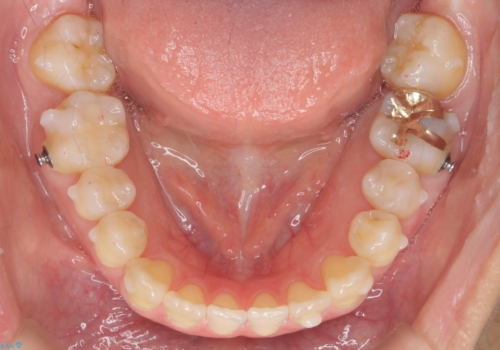

前歯のがたつき 若干受け口 インビザラインで

治療症例の内容

- 前歯のねじれおよび下の前歯が前に出ていることを気にして来院。

インビザラインで治療をおこないました。

前歯のねじれもなおり、比較的短期間でご満足いただけました。

部分矯正コースでしたので左下67の段差は特に治しておりません。

右下567及び左下6の虫歯治療も一緒に行っています。